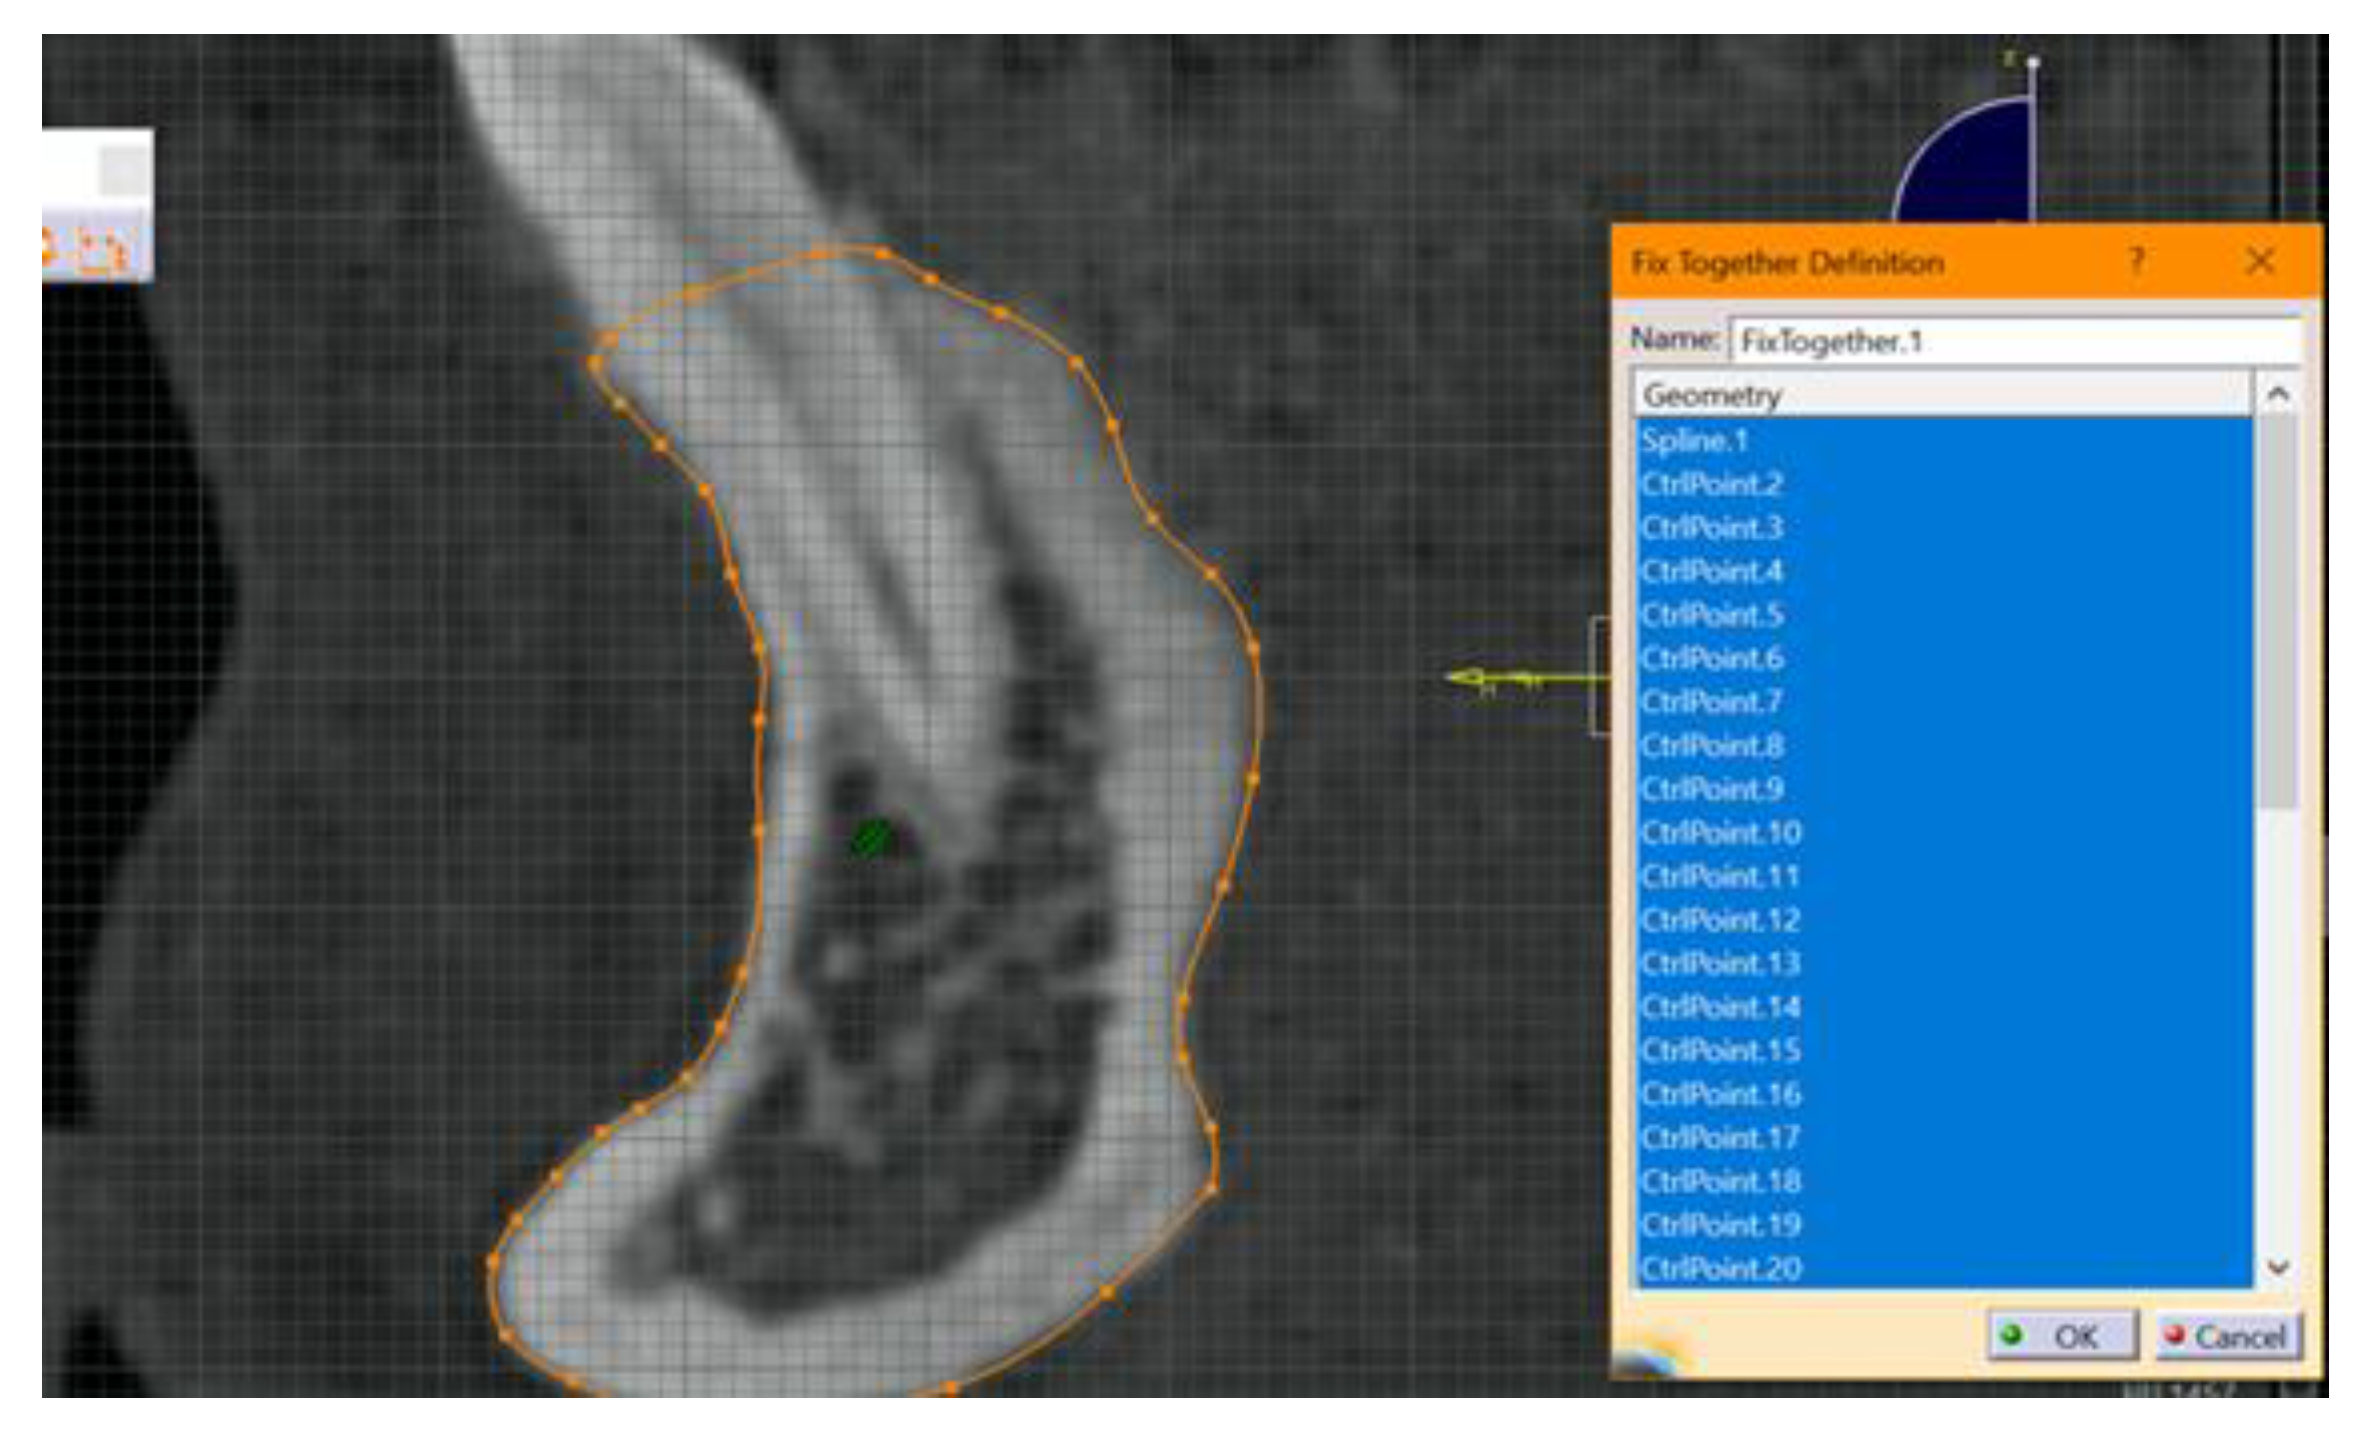

- The next step included fixing and “constraining” the obtained contour. This step is mandatory for each 2D entity in the sections obtained. The constraint aims to fix the points introduced to create curves. If this step is not performed, there is a high risk of error. This step was performed by using the fixed together tool from the Constraints menu. A dimensional constraint was also applied, with the aim of fixing the position of all points in relation to the origin of the work plane (Figure 2).